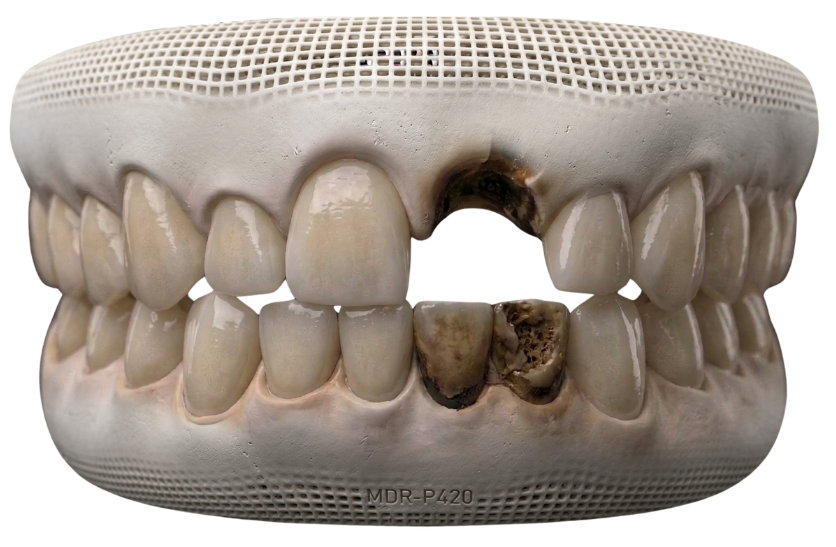

Severe Tooth Decay

Extensive decay may require a crown to restore the tooth’s structure and protect it from further damage.